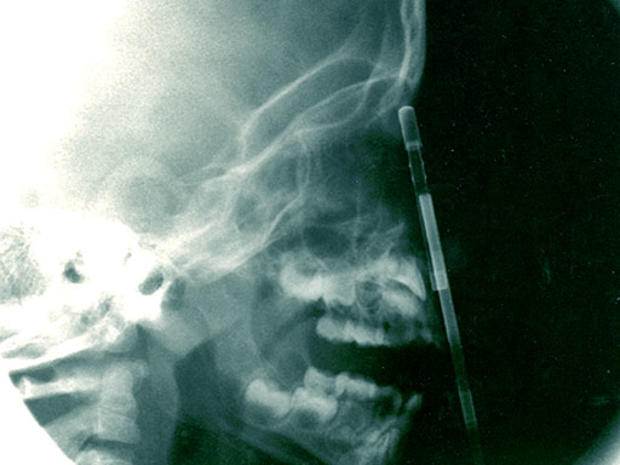

This tomography scan released Thursday, Aug. 16, 2012 by the Miguel Couto hospital, shows the skull of 24-year-old construction worker Eduardo Leite after it was pierced by a metal bar in Rio de Janeiro, Brazil. Doctors say Leite survived after a 6-foot metal bar fell from above him and pierced his head. Doctor's reportedly successfully withdrew the iron bar during a five-hour-long surgery.

Spear gun

16-year-old Yasser Lopez of Miami was injured when a spear gun his friend was holding accidentally discharged, causing a spear more than three-feet long to impale his skull and brain. Amazingly the teen survived, and was even able to speak to doctors throughout the whole ordeal.